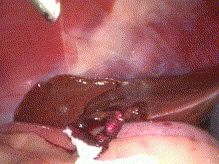

Gastrointestinal Laparoscopy in Small Animals

» Photos